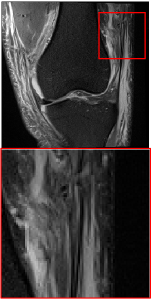

Figure 5 provides the qualitative comparison of the various methods on the four datasets at a scale of 4. The top, second, third, and bottom rows are the SR results under the FastMRI, clinical brain, clinical tumor and clinical pelvic datasets, respectively. The red boxes indicate the zoom-in region of complicated anatomical structures along with their corresponding error maps. Note that the brighter textures in the error maps, the lower the quality of the reconstructed images. As can be seen, compared to methods based on Transformers and CNNs, diffusion-based methods like DisC-Diff and DiffMSR (Ours) are capable of reconstructing high-realistic images with promising reconstruction metric scores (PSNR and SSIM). Nevertheless, while DisC-Diff can reconstruct high-precision MR images, it does not preserve the structure present in the original HR images, introducing some additional information that can affect medical diagnosis. In contrast, our method combines DM and PLWformer, which can preserve the original image’s structure while restoring high-frequency information.

In this section, we present more visual qualitative comparisons. Figures 8, 9, 10, and 11 show the reconstruction results of each method in FastMRI, clinical brain, clinical tumor, and clinical pelvic, respectively. As can be seen, although DisC-Diff can reconstruct MR images with high-frequency information, it fails to preserve the structure and content of the original Target HR image effectively, resulting in image distortion. In contrast, our proposed DiffMSR can restore high-frequency information while preserving the structure of the original HR image, indicating the effectiveness of the joint use of DM and PLWformer.